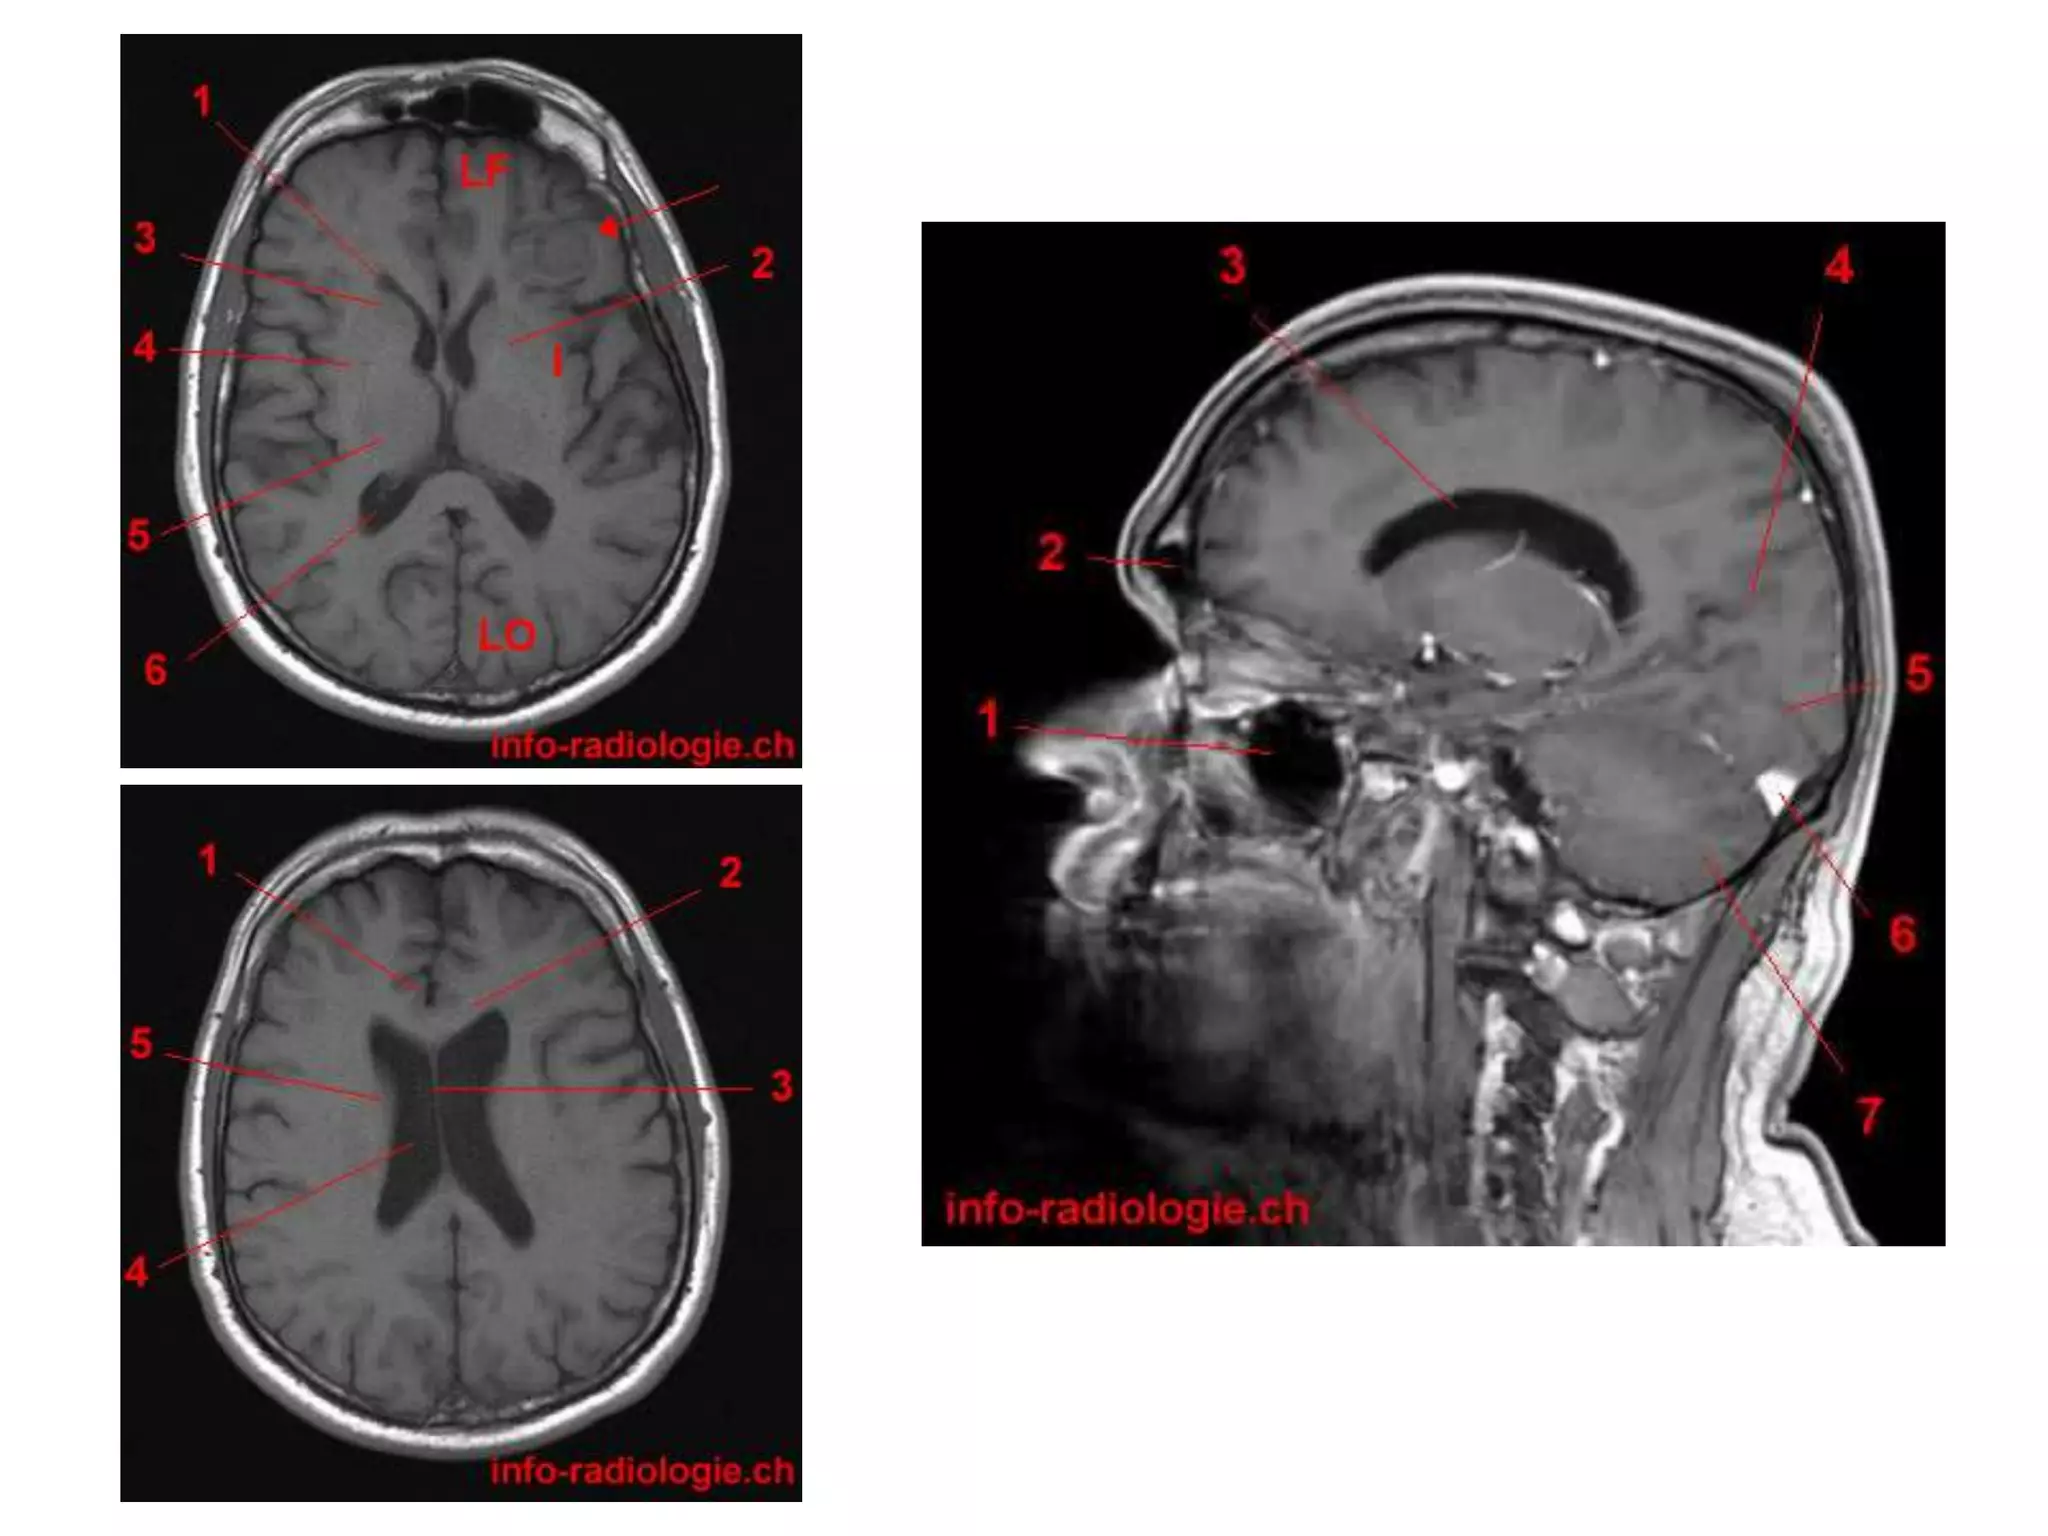

• Saggital and Coronal T1 weighted MRI – accurate

assessment of ventricles and C. callosum

• Mid Saggital section – for shape and configuration

of Aqueduct of Sylvius.

• Radiology –

Axial MRI / CT : frontal horns separated by

S. pellucidum and posteriorly lateral ventricles diverge

and pass into temporal and occipital horns.

Saggital MRI : ‘C’ shaped , curving round the

thalamus.

Coronal : frontal horns – inverted triangle

body – flattened

temporal horns – like ‘C’ on its sides.